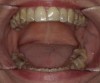

Fig 8. The appliance worn during treatment, anterior view (Fig 8), right side view (Fig 9), left side view (Fig 10), and upper arch view (Fig 11).

Figure 8

Fig 9. The appliance worn during treatment, anterior view (Fig 8), right side view (Fig 9), left side view (Fig 10), and upper arch view (Fig 11).

Figure 9

Intraoral scans were taken to document the patient's entire palate and bite registration. Scans were sent to the clinical team for the fabrication of a clear aligner/sleep appliance for the patient to wear; the chosen appliance fits over clear aligners, regardless of the tray number the patient may need (Figure 7 through Figure 11).

After the appliance was delivered, additional photographs were taken with the camera to ensure that the appliance was delivered as intended, to document the case, and to show the patient the ideal fit of the appliance in his mouth as instructions were reviewed with him.